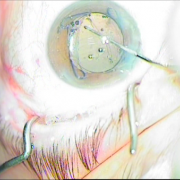

Οι σύγχρονες μικροχειρουργικές τεχνικές αποβλέπουν στον ελάχιστο τραυματισμό του οφθαλμού και στην τοποθέτηση του τεχνητού ενδοφακού στην φυσική του θέση που είναι ο οπίσθιος θάλαμος. Οι ασθενείς απολαμβάνουν τα πλεονεκτήματα των επεμβάσεων μικρής τομής χωρίς ράμματα, με άμεση αποκατάσταση της όρασης και χωρίς μετεγχειρητικό αστιγματισμό.

καταρράκτης με τραυματική

ρήξη οπ.περιφάκιου από

έγγχυση ANTIVGEF παράγοντα

του οπ. περιφάκιου